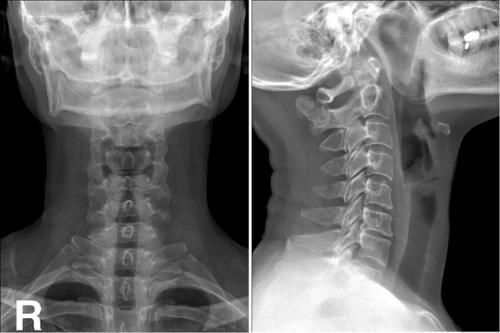

Case3:F,51y;颈2棘突单发性骨软骨瘤。

文章插图